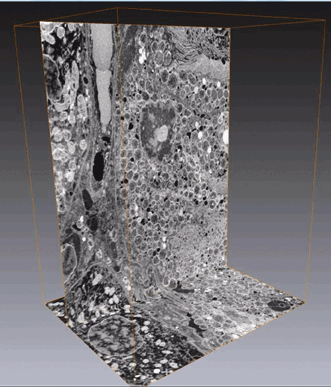

Using QCLs for MIR-Based Spectral Imaging — Applications in Tissue Pathology

H. Sreedhar*1, V. Varma*2, A. Graham3, Z. Richards1, F. Gambacorata4, A. Bhatt1, P. Nguyen1, K. Meinke1, L. Nonn1, G. Guzman1, E. Fotheringham5, M. Weida5, D. Arnone5, B. Mohar5, J. Rowlette5 1 Department of Bioengineering, University of Illinois at...

BioPhotonics, September 2015